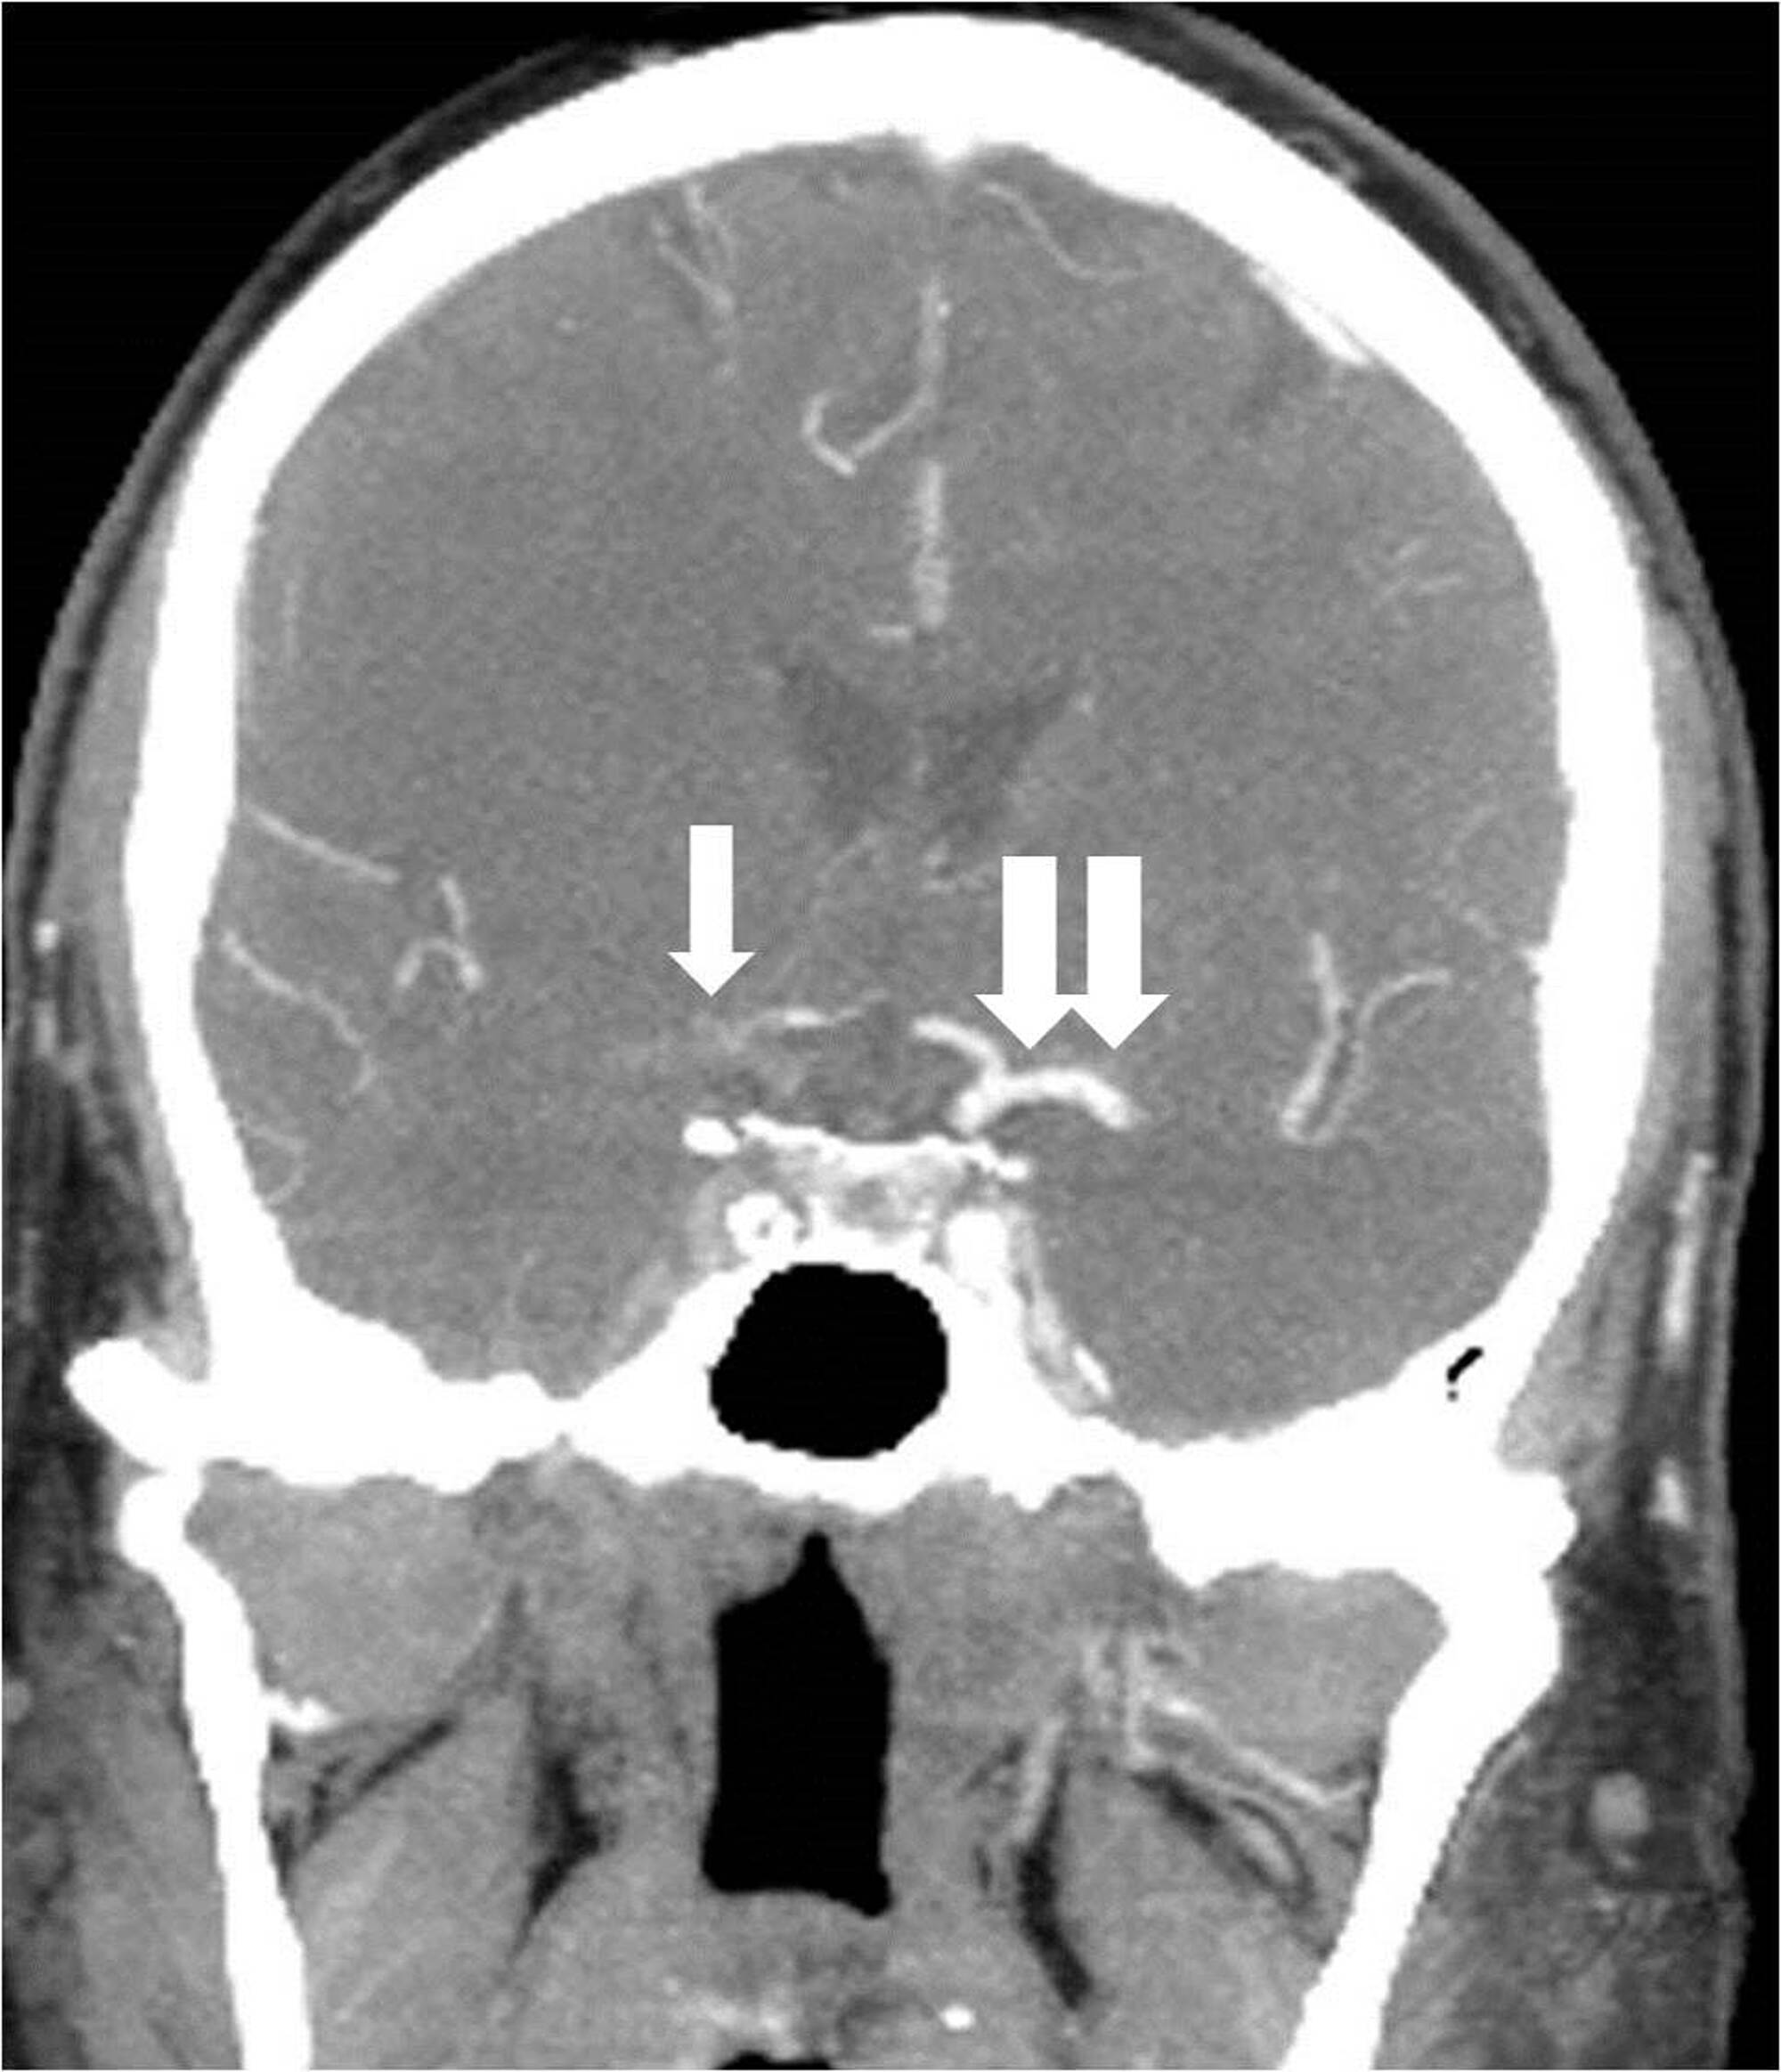

The right MCA and right anterior cerebral arteries (ACAs) could not be visualized, and multifocal embolic filling defects were detected within the cavernous and supraclinoid ICA segments on microcatheter contrast injection past the carotid origin occlusion (Figure 7).